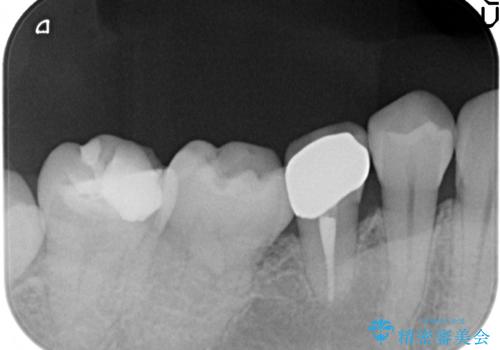

- 右下の奥歯がズキズキ痛むので診て欲しいといらっしゃった方の症例です。

右下5は虫歯が大きく神経は保存不可能だったため、根管治療を行った後、オールセラミッククラウンによる補綴を行いました。

今回用いたオールセラミッククラウンはジルコニアフレームという白い素材の上にセラミックを盛っているため、審美性が非常に高いのが特徴です。

また、ジルコニアは人工ダイヤモンドの材料にも使われているほど高い強度を持っており、そのためオールセラミッククラウンは審美性だけでなく、奥歯やブリッジの補綴も可能とするクラウンです。